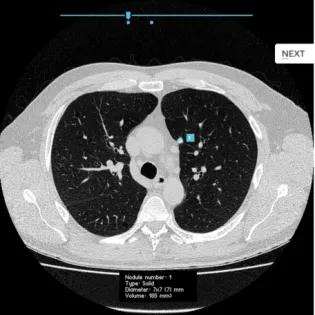

We are involved in early studies of CT lung cancer screening as well as incorporation of artificial intelligence tools for lung nodule detection, follow-up and management. HTML OverviewLung cancer is one of the most fatal cancers, with a poor outcome mostly due to late detection. The early identification of lung nodules is vital to ensure early stage (and treatable/curable) lung cancer is diagnosed. Edinburgh Imaging is playing a central role in this, working together with clinical colleagues at NHS Lothian and academic colleagues at the Usher Institute.There are several strands to this research:Development of novel nodule detection and characterization software, which serves as a back-up for radiologists and has been shown to improve detection of these early lung nodules. Software has been rolled out across NHS Lothian for detection of lung nodules on routine chest CT. A HDRUK funded project, INPACT, will further explore the impact of this software on patient managementDevelopment of a standardized reporting template with patient management according to established guidelines, once lung nodules are detected. A European project (PINPOINT), funded by Astra Zeneca and Aidence, will evaluate the automation of lung nodule detection and lung nodule management.Support of CT based lung cancer screening, which is focused on particular groups of people who are at increased risk for developing lung cancer. This first Scottish pilot particularly aims to develop ways of including those who are hard to reach, who tend to be in underprivileged areas around Edinburgh and beyond (the LUNGSCOT study). Computed tomography (CT) scan of the chest, demonstrating artificial intelligence (AI) detected lung nodule (in blue box). These nodules are at risk of being missed by radiologists, but require appropriate follow-up to enable early lung cancer detection. Lead lung cancer researcherProf Edwin van BeekTo discuss new research & collaborative imaging projects with Edinburgh Imaging, please contact: Edinburgh Imaging Enquiries: studies / collaborations / facilities Contact details Email: edimg.studyinfo@ed.ac.uk Research staff with a lung cancer focusDavid Senyszak Prof David Weller Dr Miguel Bernabeu Llinares Dr John MurchisonDr Rishi RamaeshDr Melanie MacKeanDr Ahsan Akram Current projectsCompleted projects Funding organisations and groupsOrganisations are listed alphabetically:AidenceAstra ZenecaChief Scientist Office (CSO)Health Data Research UK (HDR UK) Relevant links 02 Dec 21. Aidence press release01 Dec 21. Lung cancer imaging09 Aug 21. Aidence & AstraZeneca AI collaboration Relevant Edinburgh Imaging publications 20 May 22. Featured Paper. Validation of a deep learning computer aided system for CT based lung nodule detection, classification, and growth rate estimation in a routine clinical population07 May 22. Featured Paper. Lung tissue shows divergent gene expression between chronic obstructive pulmonary disease and idiopathic pulmonary fibrosis Relevant publications Caulo, A., et al. Integrated imaging of non-small cell lung cancer recurrence: CT and PET-CT findings, possible pitfalls and risk of recurrence criteria. Eur Radiol 22, 588–606 (2012). https://doi.org/10.1007/s00330-011-2299-8Mirsadraee S., et al. The 7th lung cancer TNM classification and staging system: Review of the changes and implications. World J Radiol. 2012 Apr 28;4(4):128-34. doi: 10.4329/wjr.v4.i4.128. PMID: 22590666; PMCID: PMC3351680.Wild, J.M., et al. MRI of the lung (1/3): methods. Insights Imaging 3, 345–353 (2012). https://doi.org/10.1007/s13244-012-0176-xBiederer, J., et al. MRI of the lung (2/3). Why … when … how?. Insights Imaging 3, 355–371 (2012). https://doi.org/10.1007/s13244-011-0146-8Biederer, J., et al. MRI of the lung (3/3)—current applications and future perspectives. Insights Imaging 3, 373–386 (2012). https://doi.org/10.1007/s13244-011-0142-zWalker AE., et al. Chest radiographs and the elusive lung cancer. Digit Med 2016;2:120-6Lee G., et al. Radiomics and its emerging role in lung cancer research, imaging biomarkers and clinical management: State of the art. European Journal of Radiology. 2016 Sep 10. https://doi.org/10.1016/j.ejrad.2016.09.005Biederer J., J et al. Screening for lung cancer: Does MRI have a role? European Journal of Radiology. 2016 Sep 16. https://doi.org/10.1016/j.ejrad.2016.09.016for the COPDGene Investigators, van Beek E. Lung Mass in Smokers. Academic Radiology. 2017 Aug 30;24(4):386-392. https://doi.org/10.1016/j.acra.2016.10.011International Workshop for Pulmonary Functional Imaging (IWPFI), Ohno Y, Kauczor H-U, Hatabu H, Seo JB, van Beek EJR. MRI for solitary pulmonary nodule and mass assessment: Current state of the art. Journal of Magnetic Resonance Imaging. 2018 Mar 23. https://doi.org/10.1002/jmri.26009 This article was published on 2024-08-22